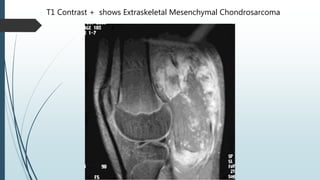

Hard mass in middle-aged man’s calf for 8 years

T1 Contrast + shows Extraskeletal Mesenchymal Chondrosarcoma